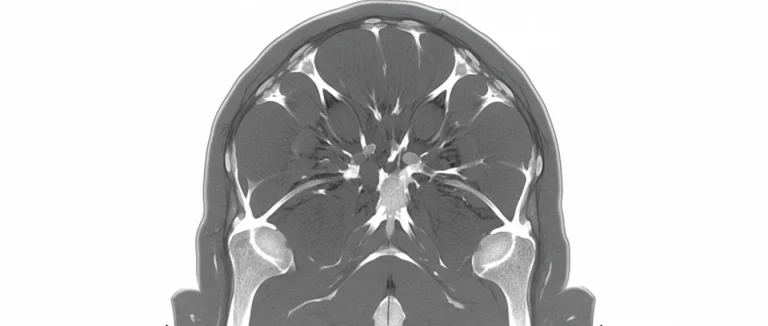

- Магнитно‑резонансная томография (MRI) – золотой стандарт для оценки состояния ротаторной манжеты, сухожилий и связок. Позволяет различать растяжение от частичного разрыва.

- Ультразвуковое исследование (УЗИ) – быстрый и доступный способ визуализировать надостную мышцу и подостную область, особенно в динамике при движении.

- Рентгенография – используется для исключения переломов плечевой кости и оценки положения суставных поверхностей.

В Лив Хоспитал применяется современное 3‑Тесла MRI, обеспечивающее высокое разрешение изображений без контрастных веществ, что особенно важно при подозрении на микротрещины сухожилий.

Если результаты визуализации подтверждают лишь растяжение, лечение обычно проходит без хирургического вмешательства, однако при обнаружении разрыва ротаторной манжеты (rotator cuff tear) может потребоваться эндоскопическая операция.